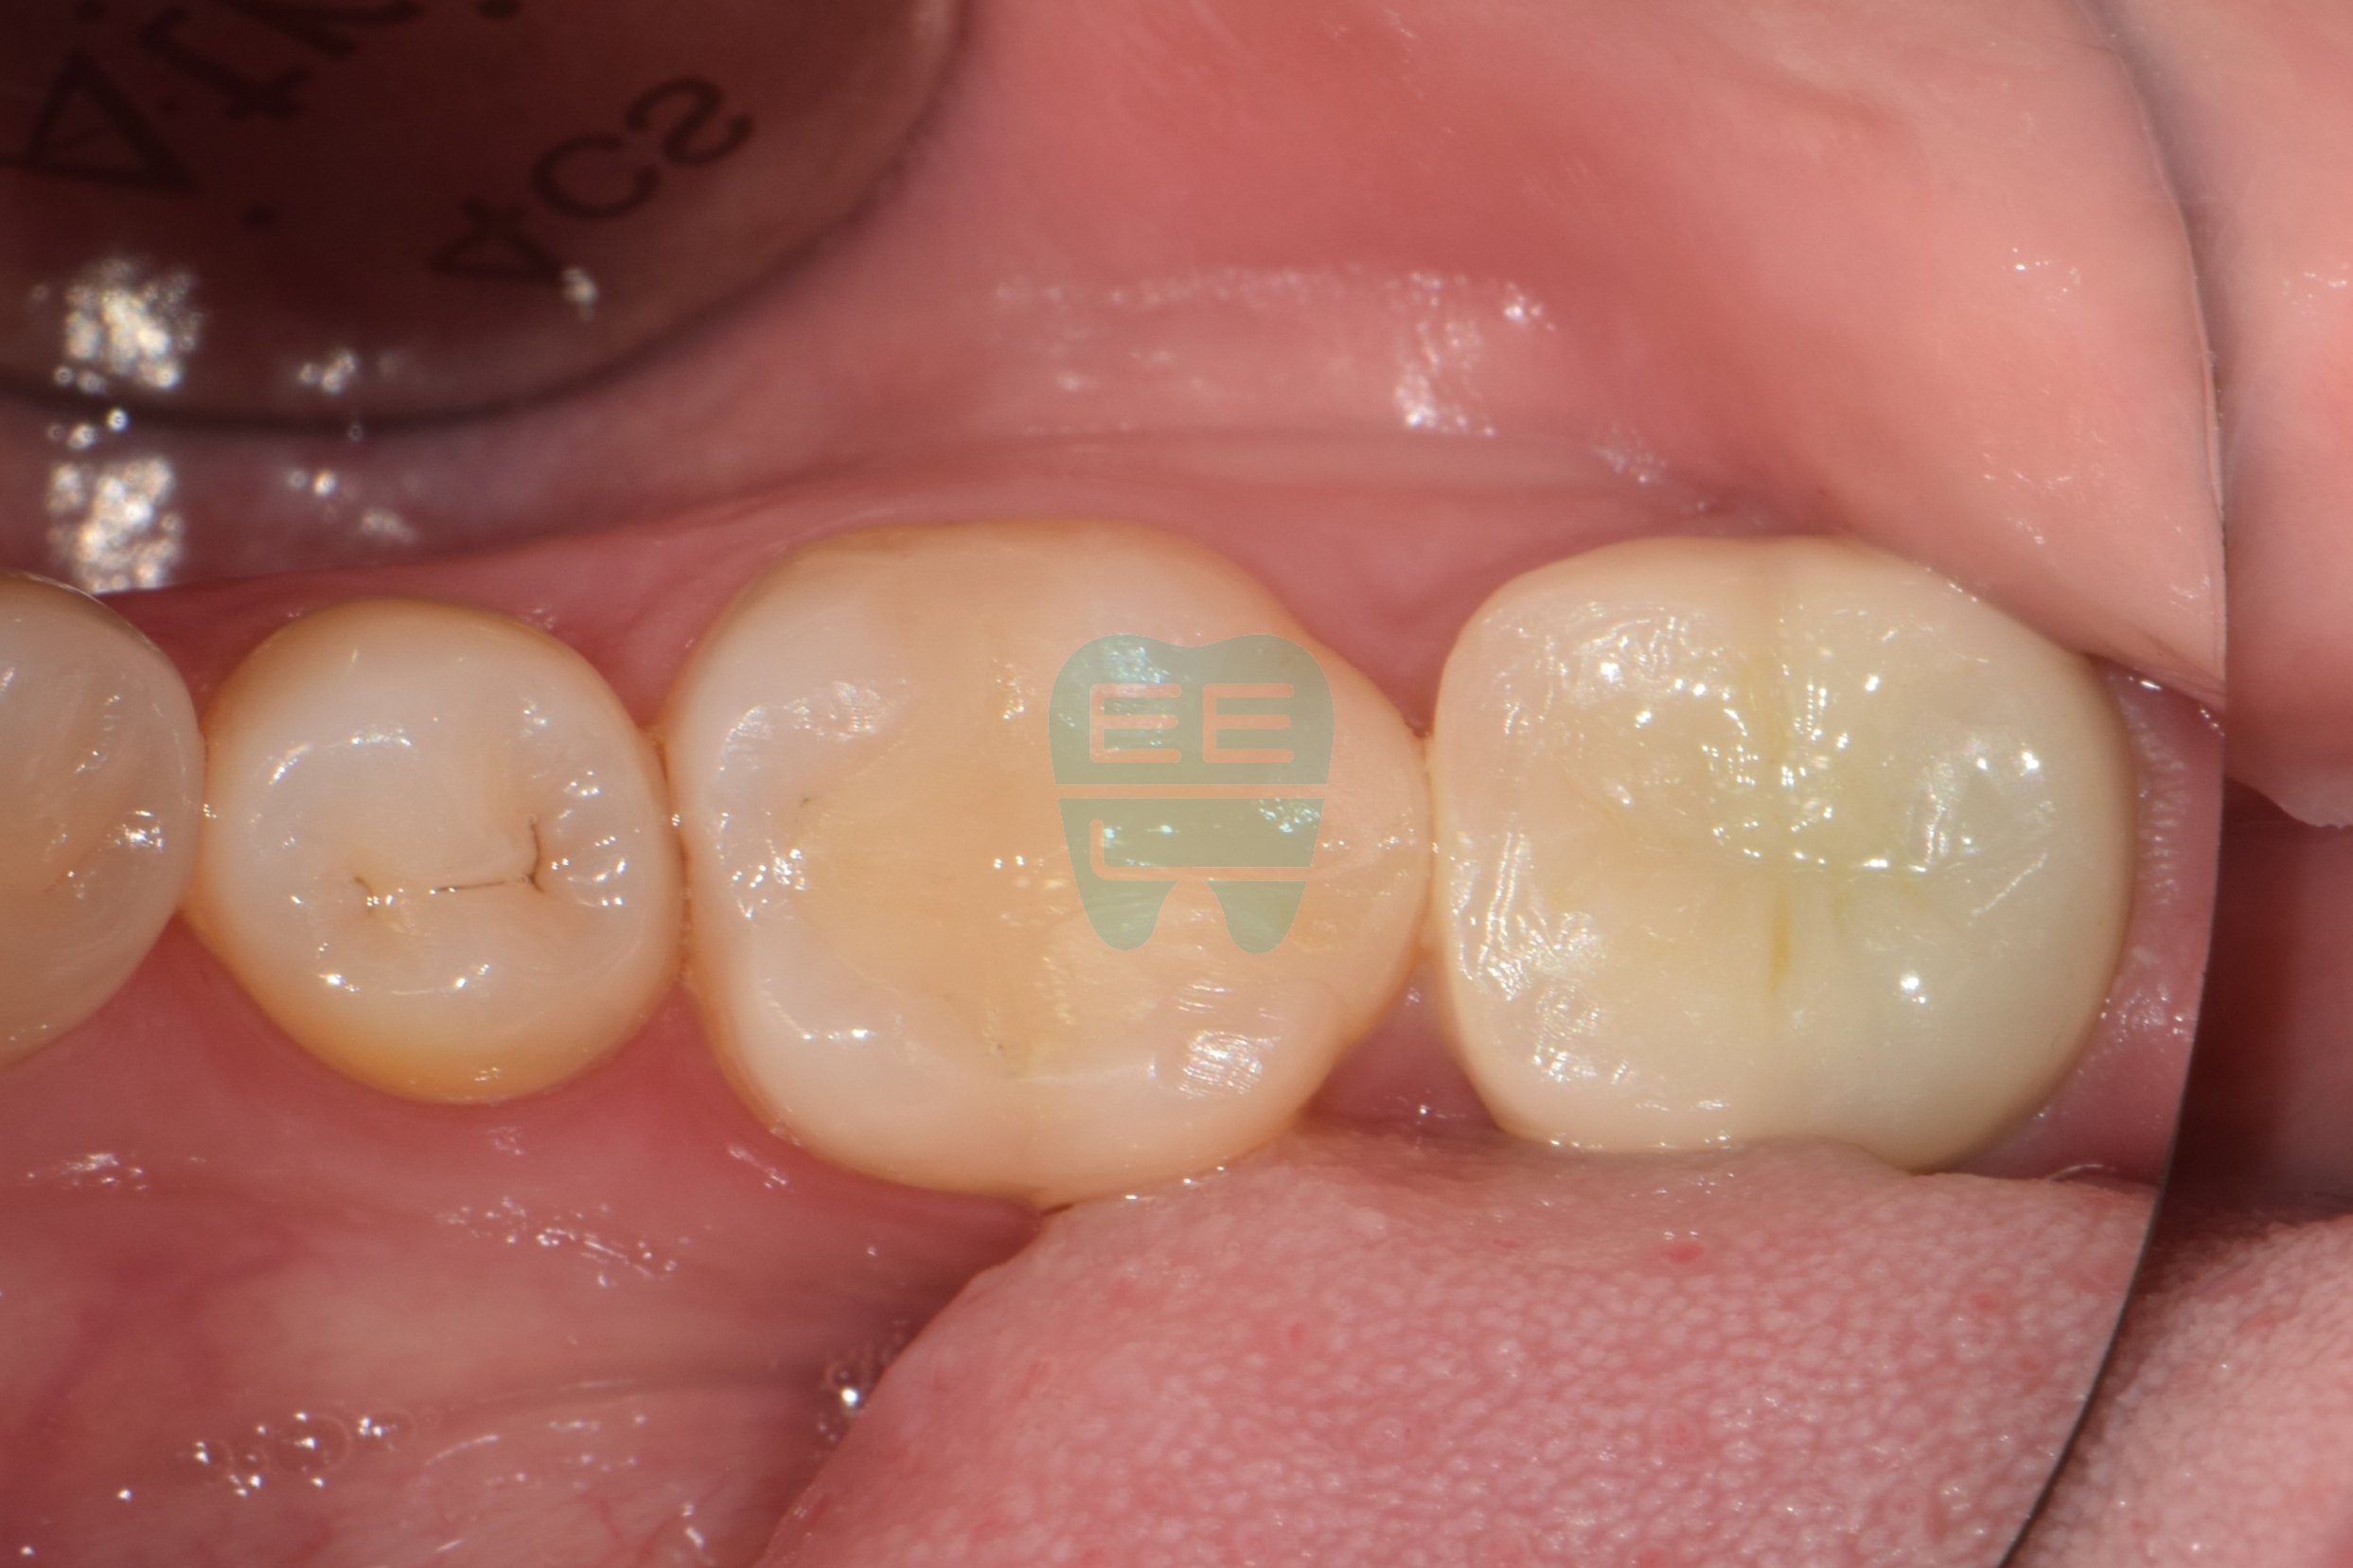

크라운 하방 2차우식 치료를 위한 레진코어 빌드업 방법

초진상태로 찝찝한 냄새가 나신다 하심크라운 제거후 상태로 파란색 코어가 관찰됨코어 제거후 상태로 원심 2차우식으로인한 leakage로인한 악취로 진단함충치와 레진코어를 모두 제거한 상태러버댐과 원심 격리를 위한 매트릭스 밴드를 장착중인 모습러버댐 하에 원심 레진wall을 형성한 모습

사진 1